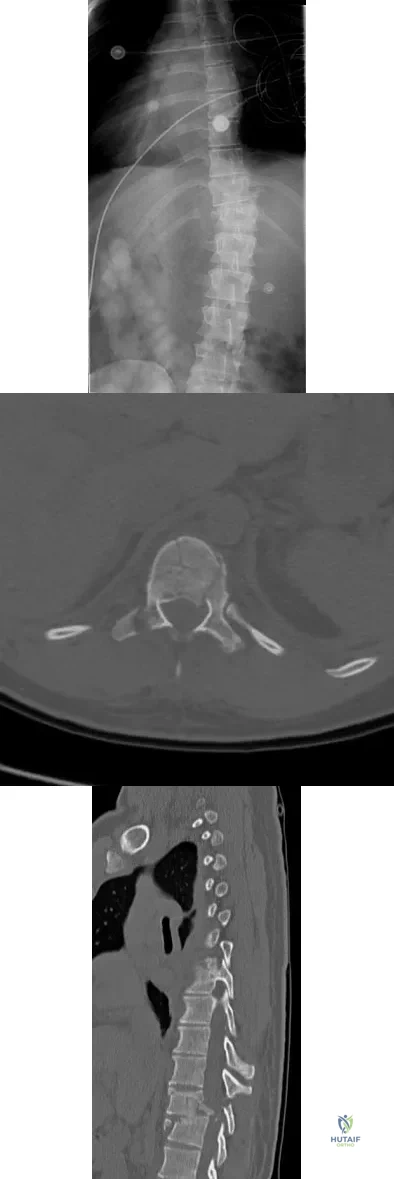

A skeletally mature 15-year-old girl who was thrown from the car in a rollover accident sustained the injuries shown in Figures 23a through 23d. Examination reveals no neurologic deficit, but the patient has moderate posterior spinal tenderness at the level of the injury. What is the most appropriate treatment?

A 23-year-old man is involved in a motor vehicle accident. An AP radiograph is shown in Figure 29a, and axial and sagittal CT scans are shown in Figures 29b and 29c. Neurologic examination shows 1/5 strength of his quadriceps and iliopsoas on the right, with 1/5 quadriceps function on the left. Definitive treatment of his injury should consist of